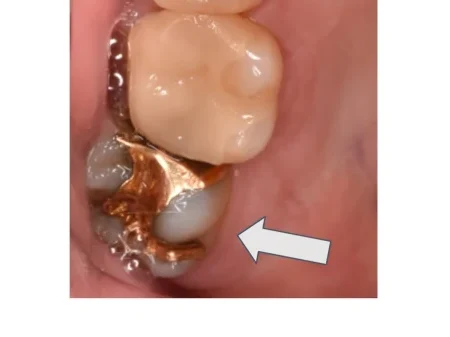

セラミック 2023.0330代男性「詰め物が浮き上がっている気がする」合わなくなったゴールドの詰め物を外して虫歯を取り除き、自然な白さで強度もあるセラミックの「E-maxインレー」で修復した症例